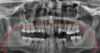

1

Q

Label the following image:

A

1. blue: mandibular body

2. yellow: angle of mandible

3. orange: ramus of mandible

4. red: symphysis

5. green: inferior border